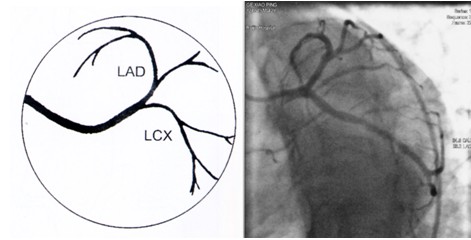

冠脉造影术简装板-绝好资料ppt

冠脉造影影像解读

冠状动脉造影,左冠状动脉造影